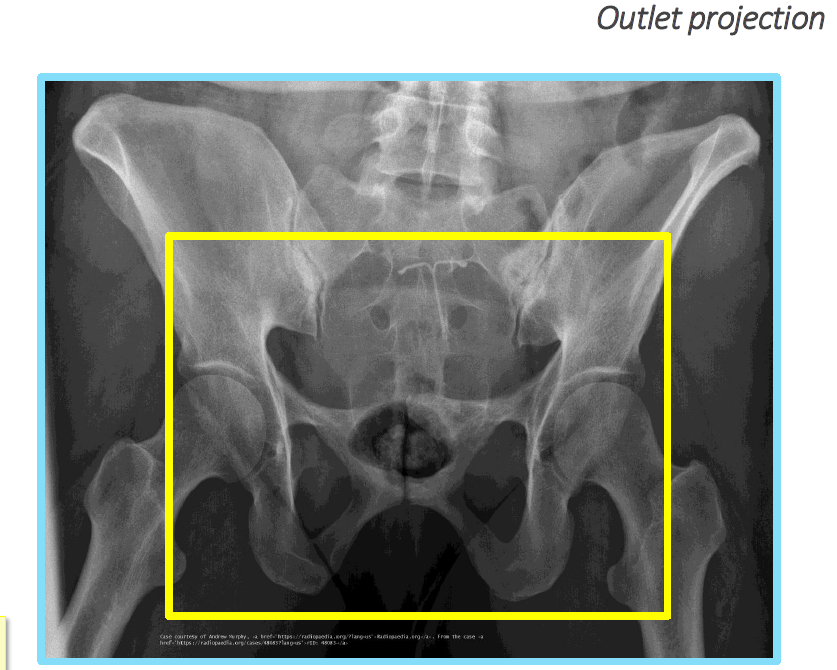

What displacement does outlet projection show?

Vertical displacement.

<p>Vertical displacement.</p>

What is the CR angle for an outlet projection (male)?

20–35° cephalad.

<p>20–35° cephalad.</p>

What anatomical structures does the outlet projection demonstrate?

Pubic and ischial bones, hip joints.

<p>Pubic and ischial bones, hip joints.</p>

What error occurs with insufficient angulation in an outlet projection?

Pubic symphysis (PS) over distal sacrum/coccyx.

<p>Pubic symphysis (PS) over distal sacrum/coccyx.</p>

What error occurs with excessive angulation in an outlet projection?

Pubic symphysis (PS) over S2.

Which view superimposes pubic rami over the sacrum?

Outlet view.

Which view shows pubic rami without foreshortening?

<p>Outlet view.</p>